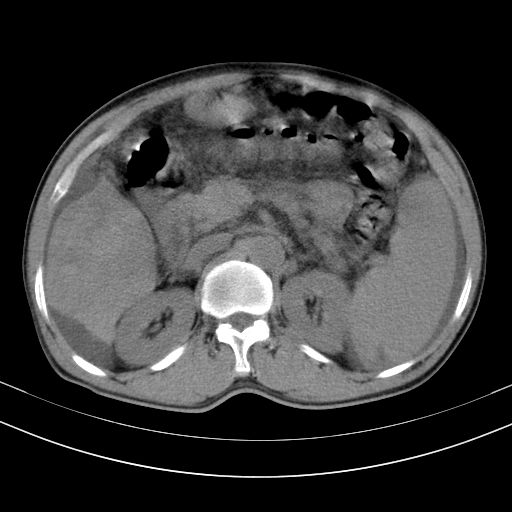

以下是引用随光逐影在2010-2-28 10:23:00的发言:[br]1)考虑肝癌;建议行ct增强扫描检查。2)肝硬化,脾大,腹水。3)慢性胆囊炎。

以下是引用dyqct在2010-2-28 16:44:00的发言:[br][quote]以下是引用随光逐影在2010-2-28 10:23:00的发言:[br]1)考虑肝癌;建议行ct增强扫描检查。2)肝硬化,脾大,腹水。3)慢性胆囊炎。